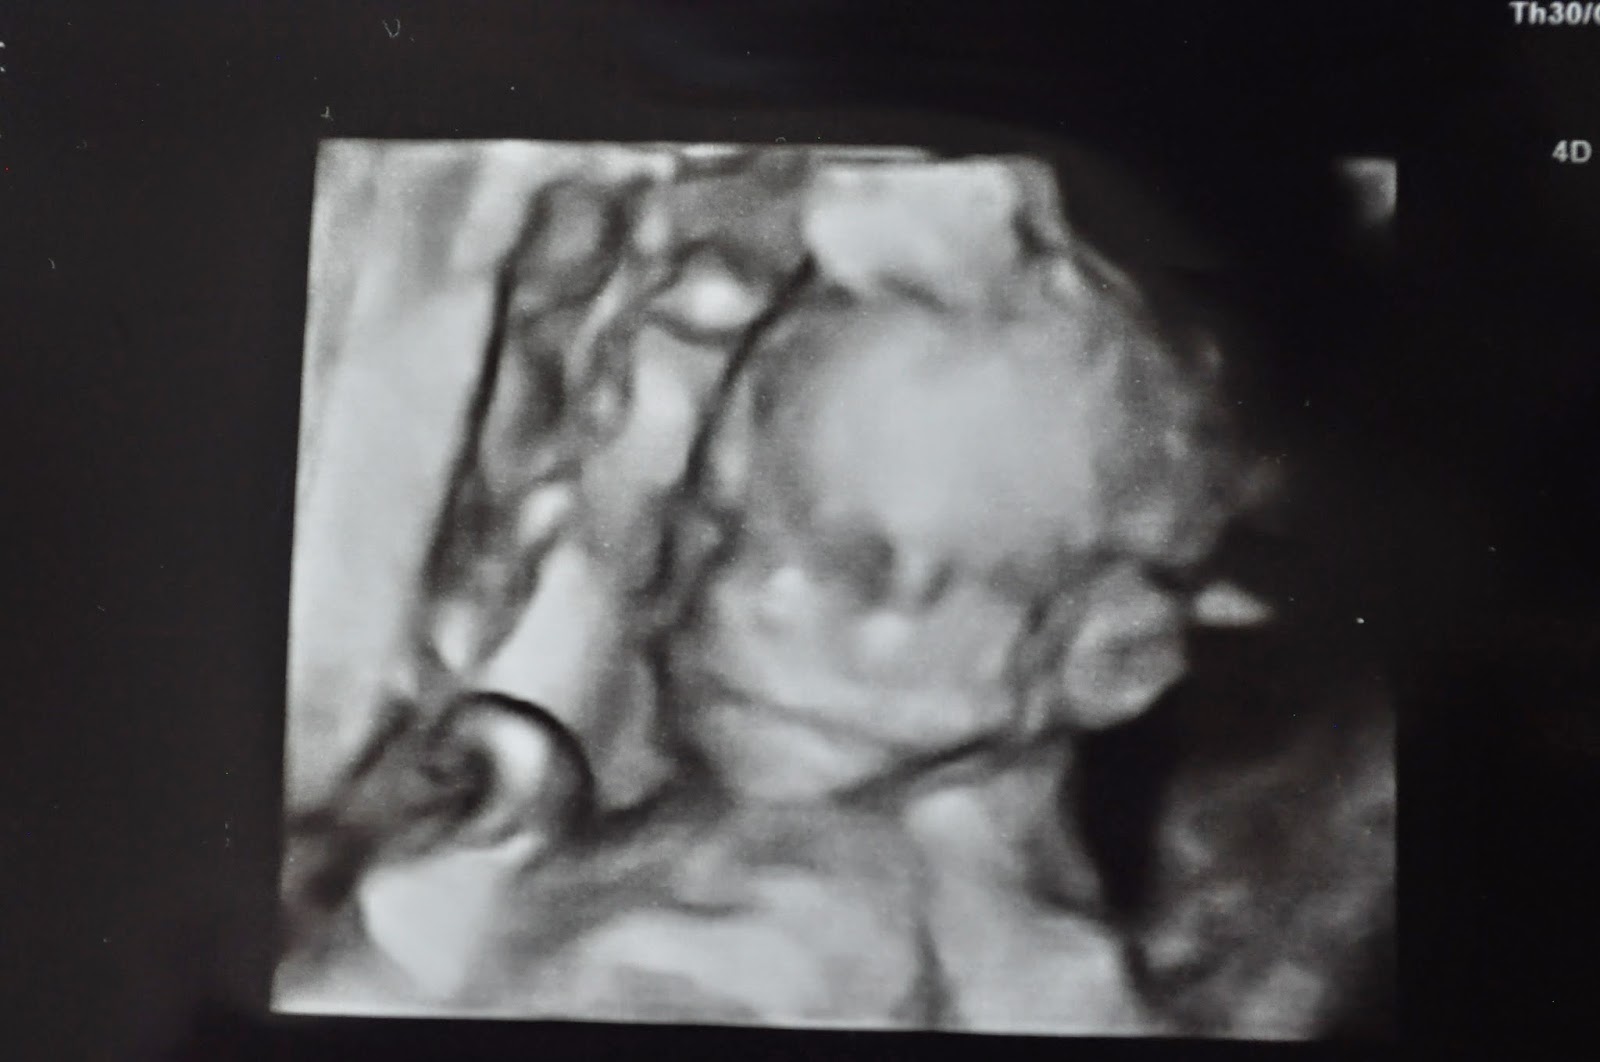

I find it unbelievable that so much detail is revealed before birth. You can see how skeletal the baby is. How it's skin sags because there is not yet any fat on it's body. The facial features.

We are 20 weeks and 5 days along on this journey. Right at the half way mark.

The heart rate was 137 today. The baby weighs 15 oz and is about the length of a tube of tooth paste.

We saw the baby making a chewing motion with it's mouth. It also had it's hand up to it's mouth and face several times. So sweet to see those precious movements. Very healthy!